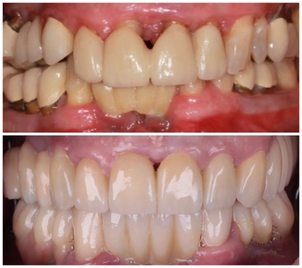

Photo de la Clinique Crillon

Quoi qu’il en soit, vérifiez toujours que votre professionnel soit spécialisé et possède une forte expérience en implantologie. De plus, il est important que vous fassiez appel à un chirurgien agréé et reconnu. Nous vous invitons pour cela à faire vos recherches sur le site du Conseil National des Médecins ou sur le site de l’Ordre National des Chirurgiens Dentistes. N’hésitez pas à visiter les forums à la recherche de commentaires et d’opinions concernant les professionnels qui vous intéressent. Il est également intéressant de visionner des photos avant/après d’anciens patients, afin d’en savoir plus sur la qualité de travail de votre médecin.

Les résultats de la pose d’implants dentaires sont généralement très satisfaisants. Il est toujours recommandé de faire appel à un chirurgien expérimenté et spécialisé pour obtenir de bons résultats :